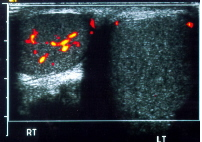

Cận lâm sàng: Công thức máu: Bạch cầu 11.9 x 109/l, Neutro:85%, Lympho: 15%. Hồng cầu: 5.17 x 1012/l, Hb: 154 g/l, Tiểu cầu: 191 x 109/l. Siêu âm Doppler: ĐM tinh hoàn phải đoạn bìu bắt phổ Doppler màu, dạng phổ 2 pha, vận tốc tâm thu đỉnh 23cm/s, vận tốc cuối tâm trương 3cm/s. Bó mạch tinh hoàn trái đoạn ống bẹn không bắt phổ Doppler màu, không khảo sát được dạng phổ. Bìu trái có cấu trúc hồi âm hỗn hợp kích thước khoảng 2x1x1cm; bên trong có cấu trúc hình ống giãn 2.7-3.5mm, chạy dạng vòng, không bắt phổ Doppler màu kể cả nghiệm pháp ép. Tinh hoàn trái bình thường, đầu mào tinh trái bị đẩy xuống dưới sát tinh hoàn trái. Kết luận: Theo dõi xoắn thừng tinh trái.

Hình 1: Hình ảnh siêu âm Doppler xoắn thừng tinh (RT: Tinh hoàn P bình thường, cấp máu tốt; LT: Tinh hoàn T có thừng tinh bị xoắn, không còn cấp máu)